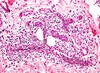

Vad ses på bilden?

Här ses utvandrade vita blodkroppar (exodat)